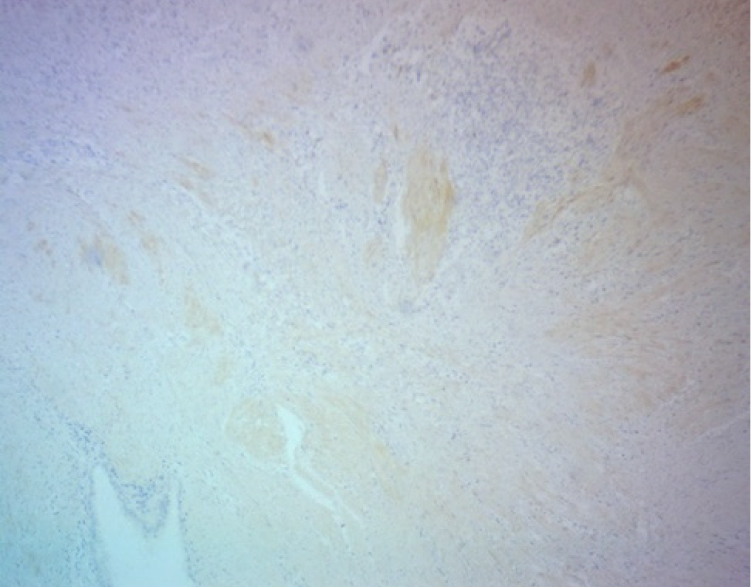

В цитогенной строме эндометриоидных гетеротопий и в соединительно тканных пролифератах была обнаружена положительная экспрессия трансформирующего фактора роста β-1. Площадь его экспрессии варьировала в разных наблюдениях от 10 до 15 % для цитогенной стромы и от 15 до 25 % для перифокально расположенных полей соединительной ткани (рис. 5).

Рис. 5. Экспрессия TGF-β1, эндометриоз послеоперационного рубца. ИГХ, ув. ×200